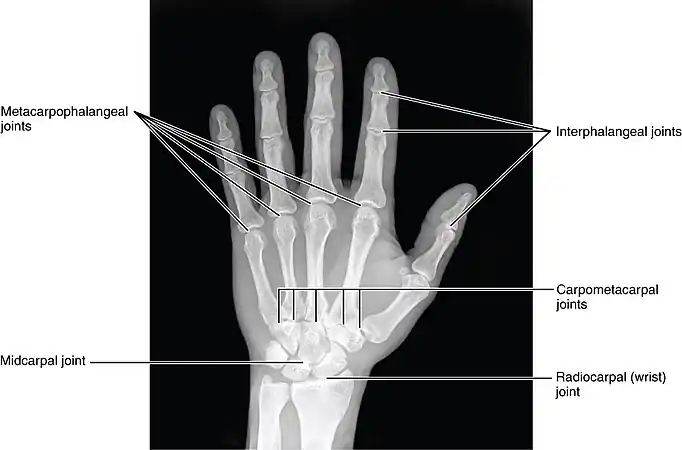

Image showing the carpal bones

The skeleton of the human hand consists of 27 bones:[10] the eight short carpal bones of the wrist are organized into a proximal row (scaphoid, lunate, triquetral and pisiform) which articulates with the bones of the forearm, and a distal row (trapezium, trapezoid, capitate and hamate), which articulates with the bases of the five metacarpal bones of the hand. The heads of the metacarpals will each in turn articulate with the bases of the proximal phalanx of the fingers and thumb. These articulations with the fingers are the metacarpophalangeal joints known as the knuckles. At the palmar aspect of the first metacarpophalangeal joints are small, almost spherical bones called the sesamoid bones. The fourteen phalanges make up the fingers and thumb, and are numbered I-V (thumb to little finger) when the hand is viewed from an anatomical position (palm up). The four fingers each consist of three phalanx bones: proximal, middle, and distal. The thumb only consists of a proximal and distal phalanx.[11] Together with the phalanges of the fingers and thumb these metacarpal bones form five rays or poly-articulated chains.

The articulations are: